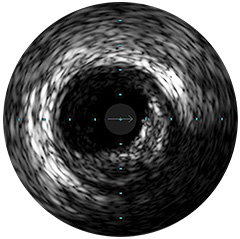

Digitale IVUS- Bildverarbeitung

-Bildverarbeitung

Bildverarbeitung